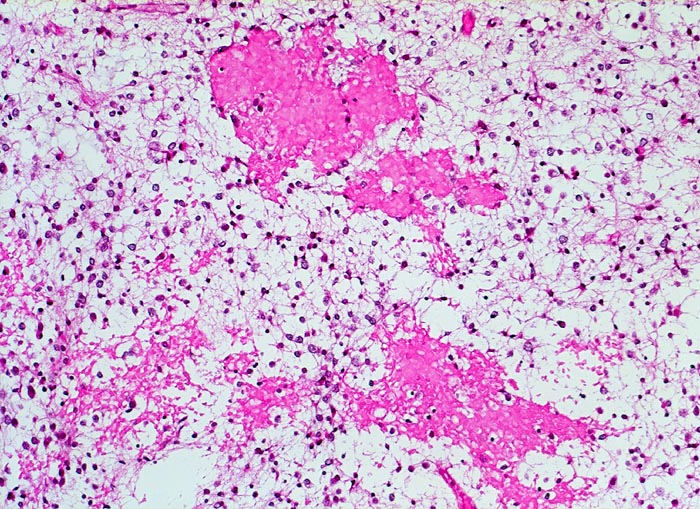

PathoPic ID 5258 - Oligodendrogliom (WHO Grad II)

Oligodendrogliom (WHO Grad II)

maligner Tumor

Hirn frontal

Nervensystem

Frische

Einblutungen

Kopfschmerzen und epileptische Anfälle seit zwei Jahren.

Oligodendrogliome zeigen häufig Einblutungen

Histologie

Vergrösserung

100

Alter

Geschlecht